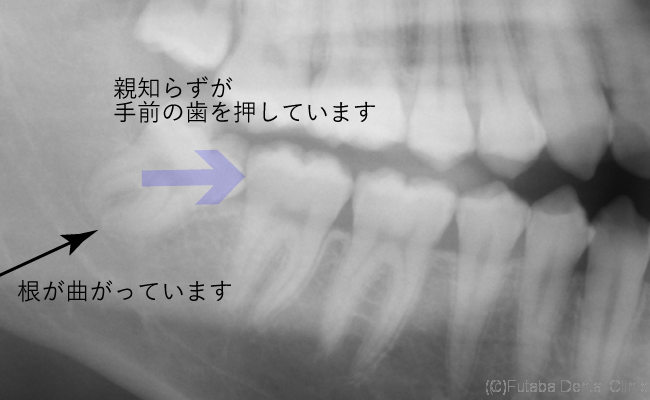

今回は、頭は出ているが、萌出するスペースがない為

手前に倒れた状態で、生えています。

しかも、手前の歯に接触している為

手前の歯を前方へ押してしまい、

前歯の歯並びが乱れる原因の一つになってしまいます。